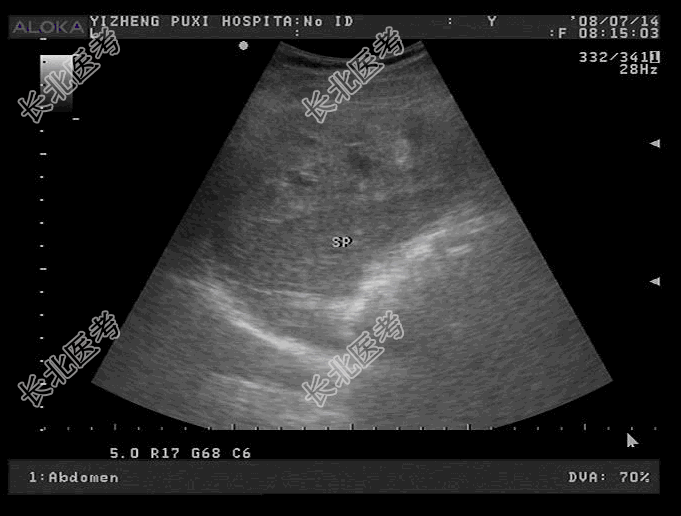

- 单项选择题患者,男, 62岁,左上腹疼痛1天。患者左侧因疼痛不能平躺, 所以只能右侧卧位查,细问病史无外伤史, 皮肤颜色尚好,二便正常。探头移到左侧发现腹腔积液深7.4cm, 超声检查如图,应考虑诊断为

A、脾淋巴瘤

B、脾血管瘤

C、脾自发性破裂

D、脾囊肿

E、脾转移性癌